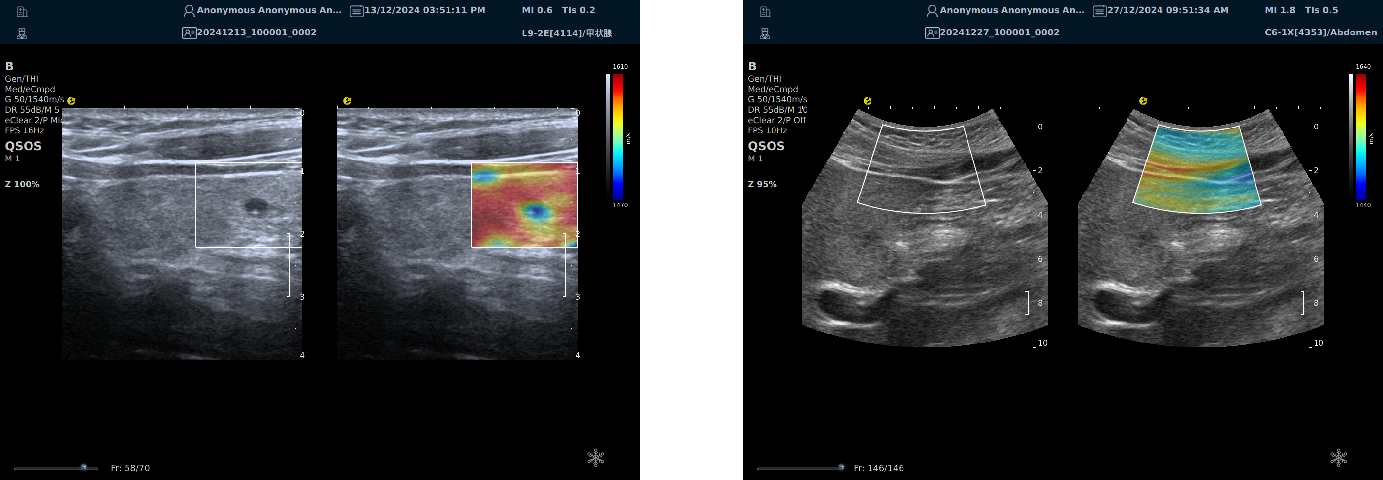

多模态复合成像

image.png与传统单一成像模式相比,多模态复合成像技术能在同一幅图像中同时呈现二维组织信息、组织血管结构及其分布,以及组织硬度信息。这种成像方式使医生能够更直观地观察病变组织的解剖结构、血液供应和硬度状况,从而为临床治疗方案的制定提供更具体、形象的参考。

image.png

声速定量成像

作为一种新兴的超声成像技术,为医学诊断和生物医学研究提供了重要的信息。利用声波在不同组织中的传播速度差异,测量每个部位的声速,并将测出来的声速通过彩色编码进行显示,生成反映组织物理特性的图像(即声速成像图),对于疾病的早期检测、诊断和治疗评估具有重要的意义。

声速定量成像给临床提供了全新的诊疗思路及工具。